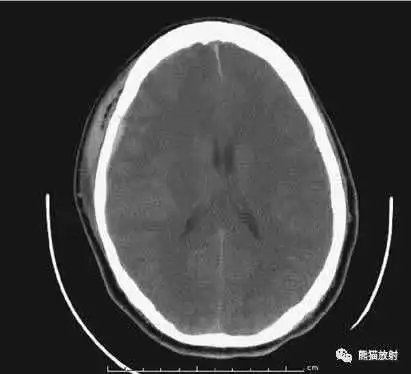

颅脑CT常用的三个窗(图A-C):

- 图A:骨窗(the bone window)

- 图B:脑窗(the brain window)

- 图C:血窗(the blood window)

图A:骨窗;主要用于明确骨折、窦腔病变、颅内积气。

图B:脑窗;可清晰显示灰白质,可发现中风的早期征象或其他导致脑水肿等表现的病变。

图C:血窗;更利于显示硬膜下或颅内出血。

本例表现:骨窗示:右顶骨骨折;三个窗均示:软组织水肿并皮下积气;血窗:少量硬膜下血肿。